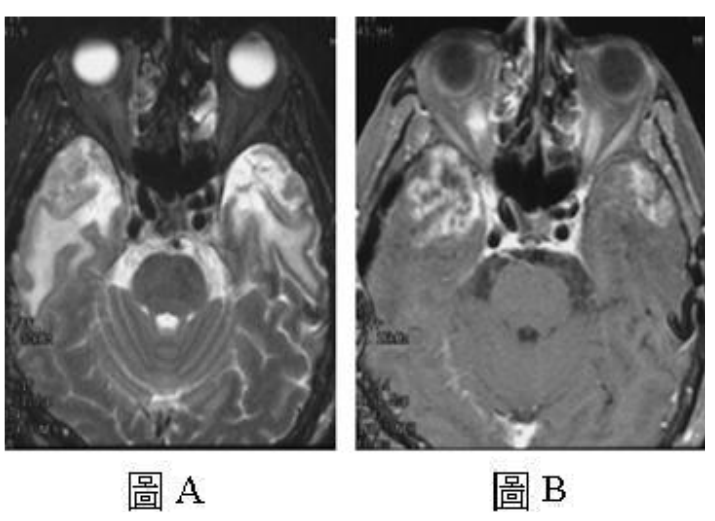

72.56歲女性患者,有鼻咽癌的病史,經放射線治療2年後,主訴頭痛,接受磁振造影檢查發現 雙側顳葉底部異常病灶,圖A為T2加權影像,圖B則為注射顯影劑後的T1影像,下列何者是 最可能的診斷?

(A)轉移性腦腫瘤(brain metastasis) (B)放射性壞死(radiation necrosis) (C)腦膿瘍(brain abscess) (D)神經膠母細胞瘤(glioblastoma)